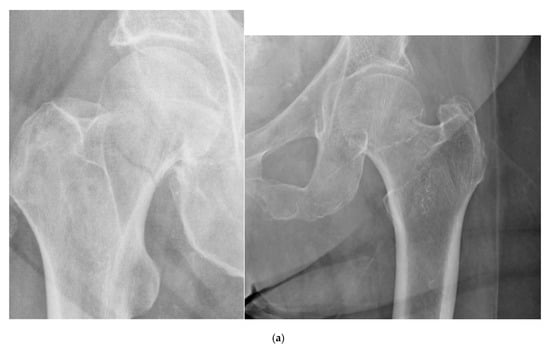

2.1. Classification of Femoral Neck Fractures

- Stage I: incomplete fracture; nondisplaced, valgus impacted

- Stage II: complete fracture; nondisplaced

- Stage III: complete fracture; partially displaced

- Stage IV: complete fracture; fully displaced